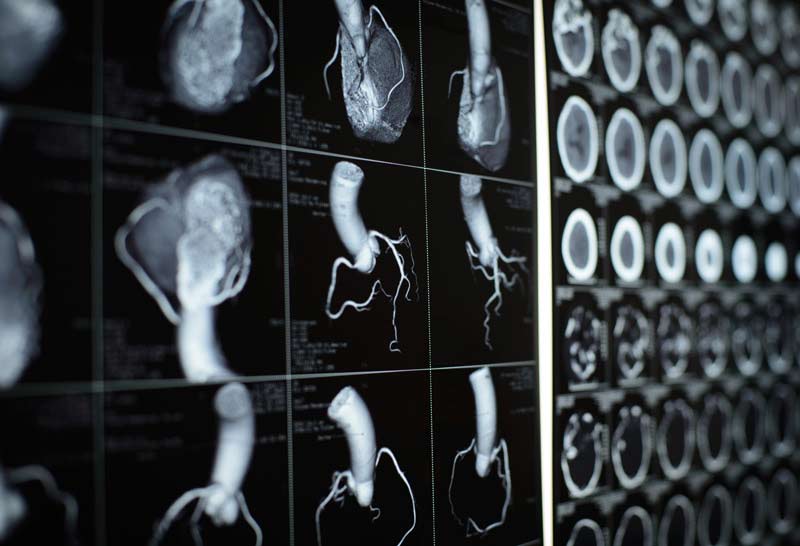

I watch the EKG screen, another pattern of waves, but limited to purely electrical activity. The heart is about 70 percent salt water. Ions like calcium, sodium, and potassium are responsible for the electrical activity that makes up the heart’s contractions. Some current leaks through to the surface of the chest and is recorded on pink graph paper. This is the electrocardiograph, or EKG, and was the first machine since Sputnik to capture my undivided attention. Two coronary arteries leave the bottom of the aorta and send blood to the heart muscle itself. We’ve snaked a JL4 (Judkins left) through the sheath and into the opening of his left coronary artery. The doctor injects contrast dye, which shows up black on the screen, and the arteries take on the aspect of tree roots. This guy’s roots have problems. He has some serious blockages, and some stents will be required.